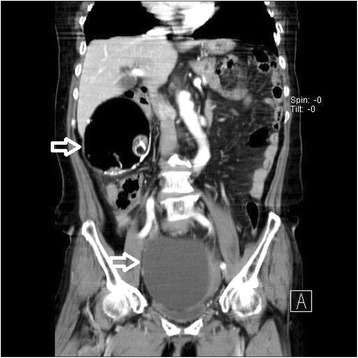

A 77-year-old Korean woman, gravida 5, para 5, was admitted through the emergency room because of lower abdominal pain, poor oral intake, and a recent increase in abdominal size for 4 days. The symptoms had gradually increased in severity. She had no history of acute pain or previous operation. Abdominal examination revealed tenderness and rebound tenderness of the lower abdomen with a palpable mass in the left lower quadrant. Ultrasound examination showed an enlarged left ovarian cyst measuring 14.3 × 14 × 8.6 cm with diffuse internal echoes, including a 6.1 × 6.0 cm hypoechogenic component without significant vascularity. The right ovary was not seen and the uterus was normal and atrophied. Contrast-enhanced computed tomography (CT) revealed an approximately 12-cm well-circumscribed mass (of fat and soft tissue density) in the pelvic cavity and a 9-cm well-circumscribed mass (of fat and soft tissue density) with calcification in the right subhepatic space (Fig. 1). The suggested preoperative diagnosis was benign teratoma of the left ovary and right subhepatic space. With regard to preoperative examination, the laboratory tests, biochemical tests, complete blood counts, blood coagulation profile, and urinalysis were all normal. The C-reactive protein (CRP) level was elevated at 6.87 (normal range 0–0.3 mg/dL), CA-125 was elevated at 50.76 (normal range 0–35 U/mL), and CA 19-9 was normal at 22.06 (normal range 0–37 U/mL). We decided to proceed with laparoscopy. Laparoendoscopic single-site surgery (LESS) was performed through a 20-mm intraumbilical incision using a Glove port (NELIS, Bucheon, South Korea). During laparoscopy, torsion of the left adnexa due to an approximately 12 × 10 cm left ovarian cyst was visualized, with an atrophied normal uterus. The left adnexa was rotated 1440° clockwise with multifocal purple discoloration and severe adhesion to the sigmoid colon (Fig. 2). The right ovary and tube could not be identified in the proper anatomical location (Fig. 3). A second cystic mass of about 10 × 7 cm was noted in the right subhepatic space. It was surrounded by thin filmy adhesions to the omentum, bowel, and appendix (Fig. 4). Left adnexectomy, intra-abdominal mass excision, and appendectomy were performed by LESS. The abdominal mass was carefully dissected from the surrounding omentum and bowel using a monopolar hook dissector and harmonic scalpel (Ethicon, Somerville, NJ, USA). There was no pedicle that needed to be clamped and no identifiable blood supply. The mass was removed intact. The entire specimen was removed through the umbilical incision without leakage of content using an EndoBag (LapBag, Sejong Medical, Paju City, South Korea). The patient recovered uneventfully and was discharged 4 days after surgery. The histopathological examination confirmed MCTs in the left ovary and right subhepatic space. The abdominal mass included ovarian tissue. These findings could also be interpreted as an autoamputation of the adnexa due to torsion of a previous ovarian cyst arising from the right ovary.

Fig. 1.

Abdominal computed tomography findings. The imaging indicates a mature cystic teratoma of the left ovary and right subhepatic space